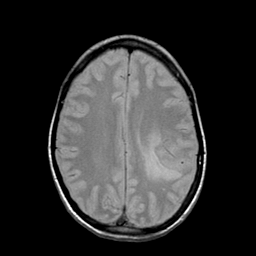

Metastatic bronchogenic carcinoma: proton density-weighted MR -- Slice #15

[Home][Help][Clinical] Slice 15